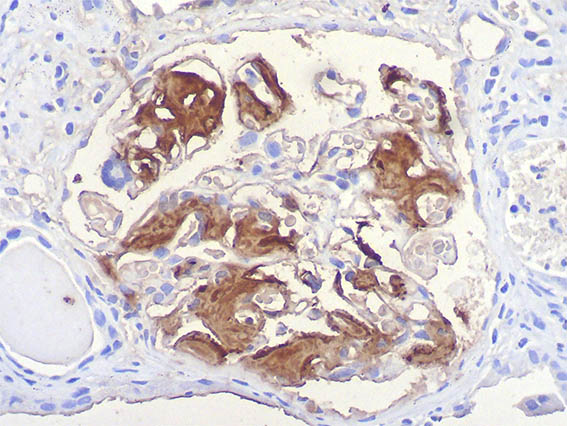

In our case, Congo red and immunostaining (Figures 12, 13, and 14) confirmed that the deposits corresponded to A amyloid. The history of secondary syphilis led us to attribute the etiology to this chronic infection.

Figure 13. Immunostaining for A amyloid, X400.

Figure 14. Immunostaining for A amyloid, X400.